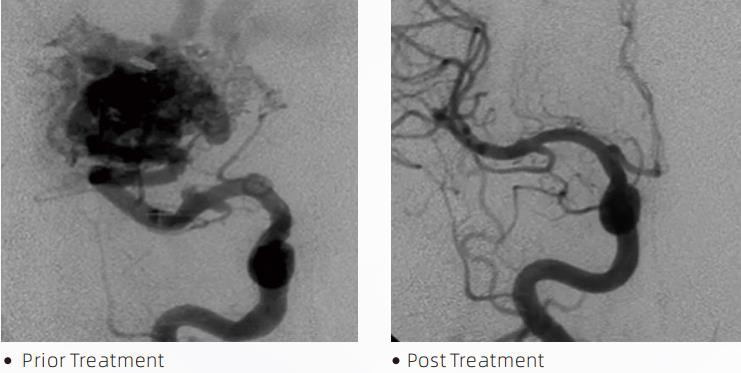

LavaTMLiquid Embolic System je interventna endovaskularna terapija za liječenje cerebrovaskularnih malformacija. Cerebrovaskularna malformacija se odnosi na grupu benignih ili malignih neurovaskularnih abnormalnosti koje mogu dovesti do intrakranijalnog krvarenja, cerebralnog infarkta, cerebralne ishemije i drugih bolesti. Sistem za tečnu embolizaciju je medicinski uređaj koji se primjenjuje jednostavnim intravaskularnim umetanjem, koji embolizira abnormalne cerebralne krvne žile ubrizgavanjem posebnog tečnog materijala. Tečni materijal formira kontroliranu emboliju tkiva unutar krvnih žila, što može smanjiti utjecaj cerebrovaskularnih malformacija na pacijente. DMSO kompatibilni mikro kateter za isporuku koji je indiciran za upotrebu u neurovaskulaturi koristi se za pristup mjestu embolizacije. Lava tekući embolični agens je neljepljivi sistem tekućih emboličkih agenasa koji se sastoji od EVOH (etilen vinil alkohola) kopolimera otopljenog u DMSO (dimetil sulfoksid) i suspendiranog mikroniziranog praha tantala kako bi se obezbijedio kontrast za vizualizaciju pod fluoroskopijom. LavaTMje dostupan u tri formulacije proizvoda, LAVA-12, LAVA-18 i LAVA-34. LAVA-12: Preporučuje se za hranjenje distalnih mikro sudova i kroz male hranilice. LAVA-18: Preporučuje se kada će se injekcije hranjenja vršiti blizu nidusa; LAVA-34: Preporučuje se za embolizaciju većeg protoka i većih fistuloznih komponenti.